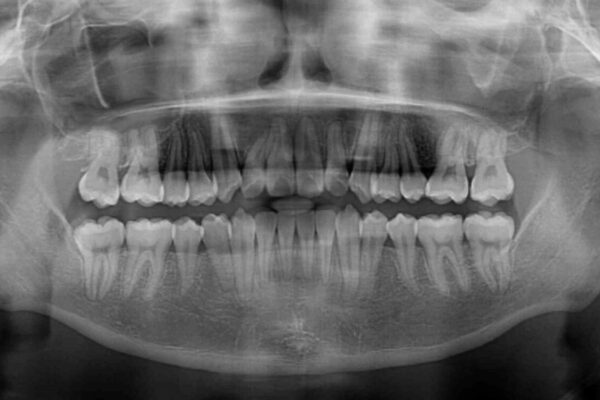

前歯のクロスバイトや八重歯の他に、左右最後臼歯のシザーズバイト(鋏状咬合)が認められました。

シザーズバイト改善のために補助装置を使用しながら、ワイヤー装置にて全体の歯列を整えることとしました。

治療前